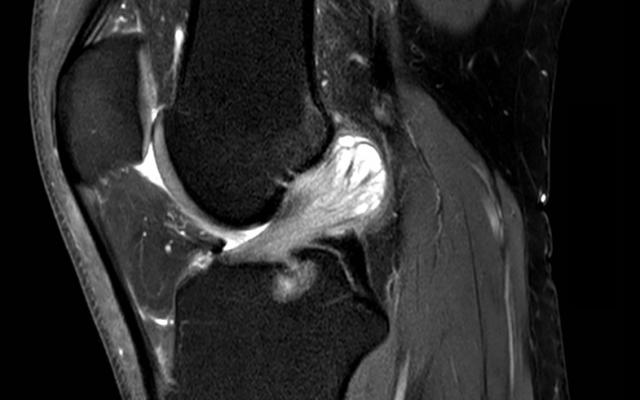

Dit artikel is alleen beschikbaar als PDF.Lees de PDF Artikelinformatie Online verschenen op 11 augustus 1932 Citeer dit artikel als Ned Tijdschr Geneeskd. 1932;76:3773-4 Heb je nog vragen na het lezen van dit artikel? Check onze AI-tool en verbaas je over de antwoorden. ASK NTVG Ook interessant Nieuws Nieuw Tijdschrift 'Maandblad voor praktische verloskunde, hoofdzakelijk ten dienste van vroedvrouwen' Nieuws De nieuwe Wet op de onteigeningen in België, hoofdzakelijk ook in het belang der hygieine tot stand gebragt Beeldquiz Een man met een pijnlijke knie met flexiebeperking Meer gerelateerd … Reacties Login om een reactie te plaatsen